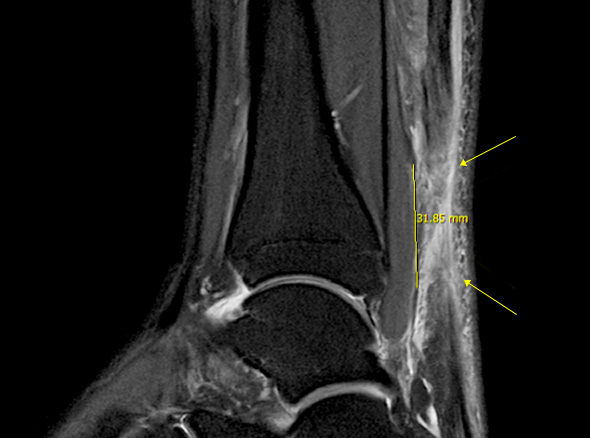

발뒤꿈치 뼈와 종아리 근육을 연결하는 아킬레스건이 부분적으로 또는 완전히 찢어지는 손상입니다.

아킬레스건은 우리 몸에서 가장 크고 강력한 힘줄 중 하나로, 걷기, 뛰기, 점프 등의 동작을 수행하는 데 중요한 역할을 합니다.

* 환자에게 받은 소중한 자료입니다.